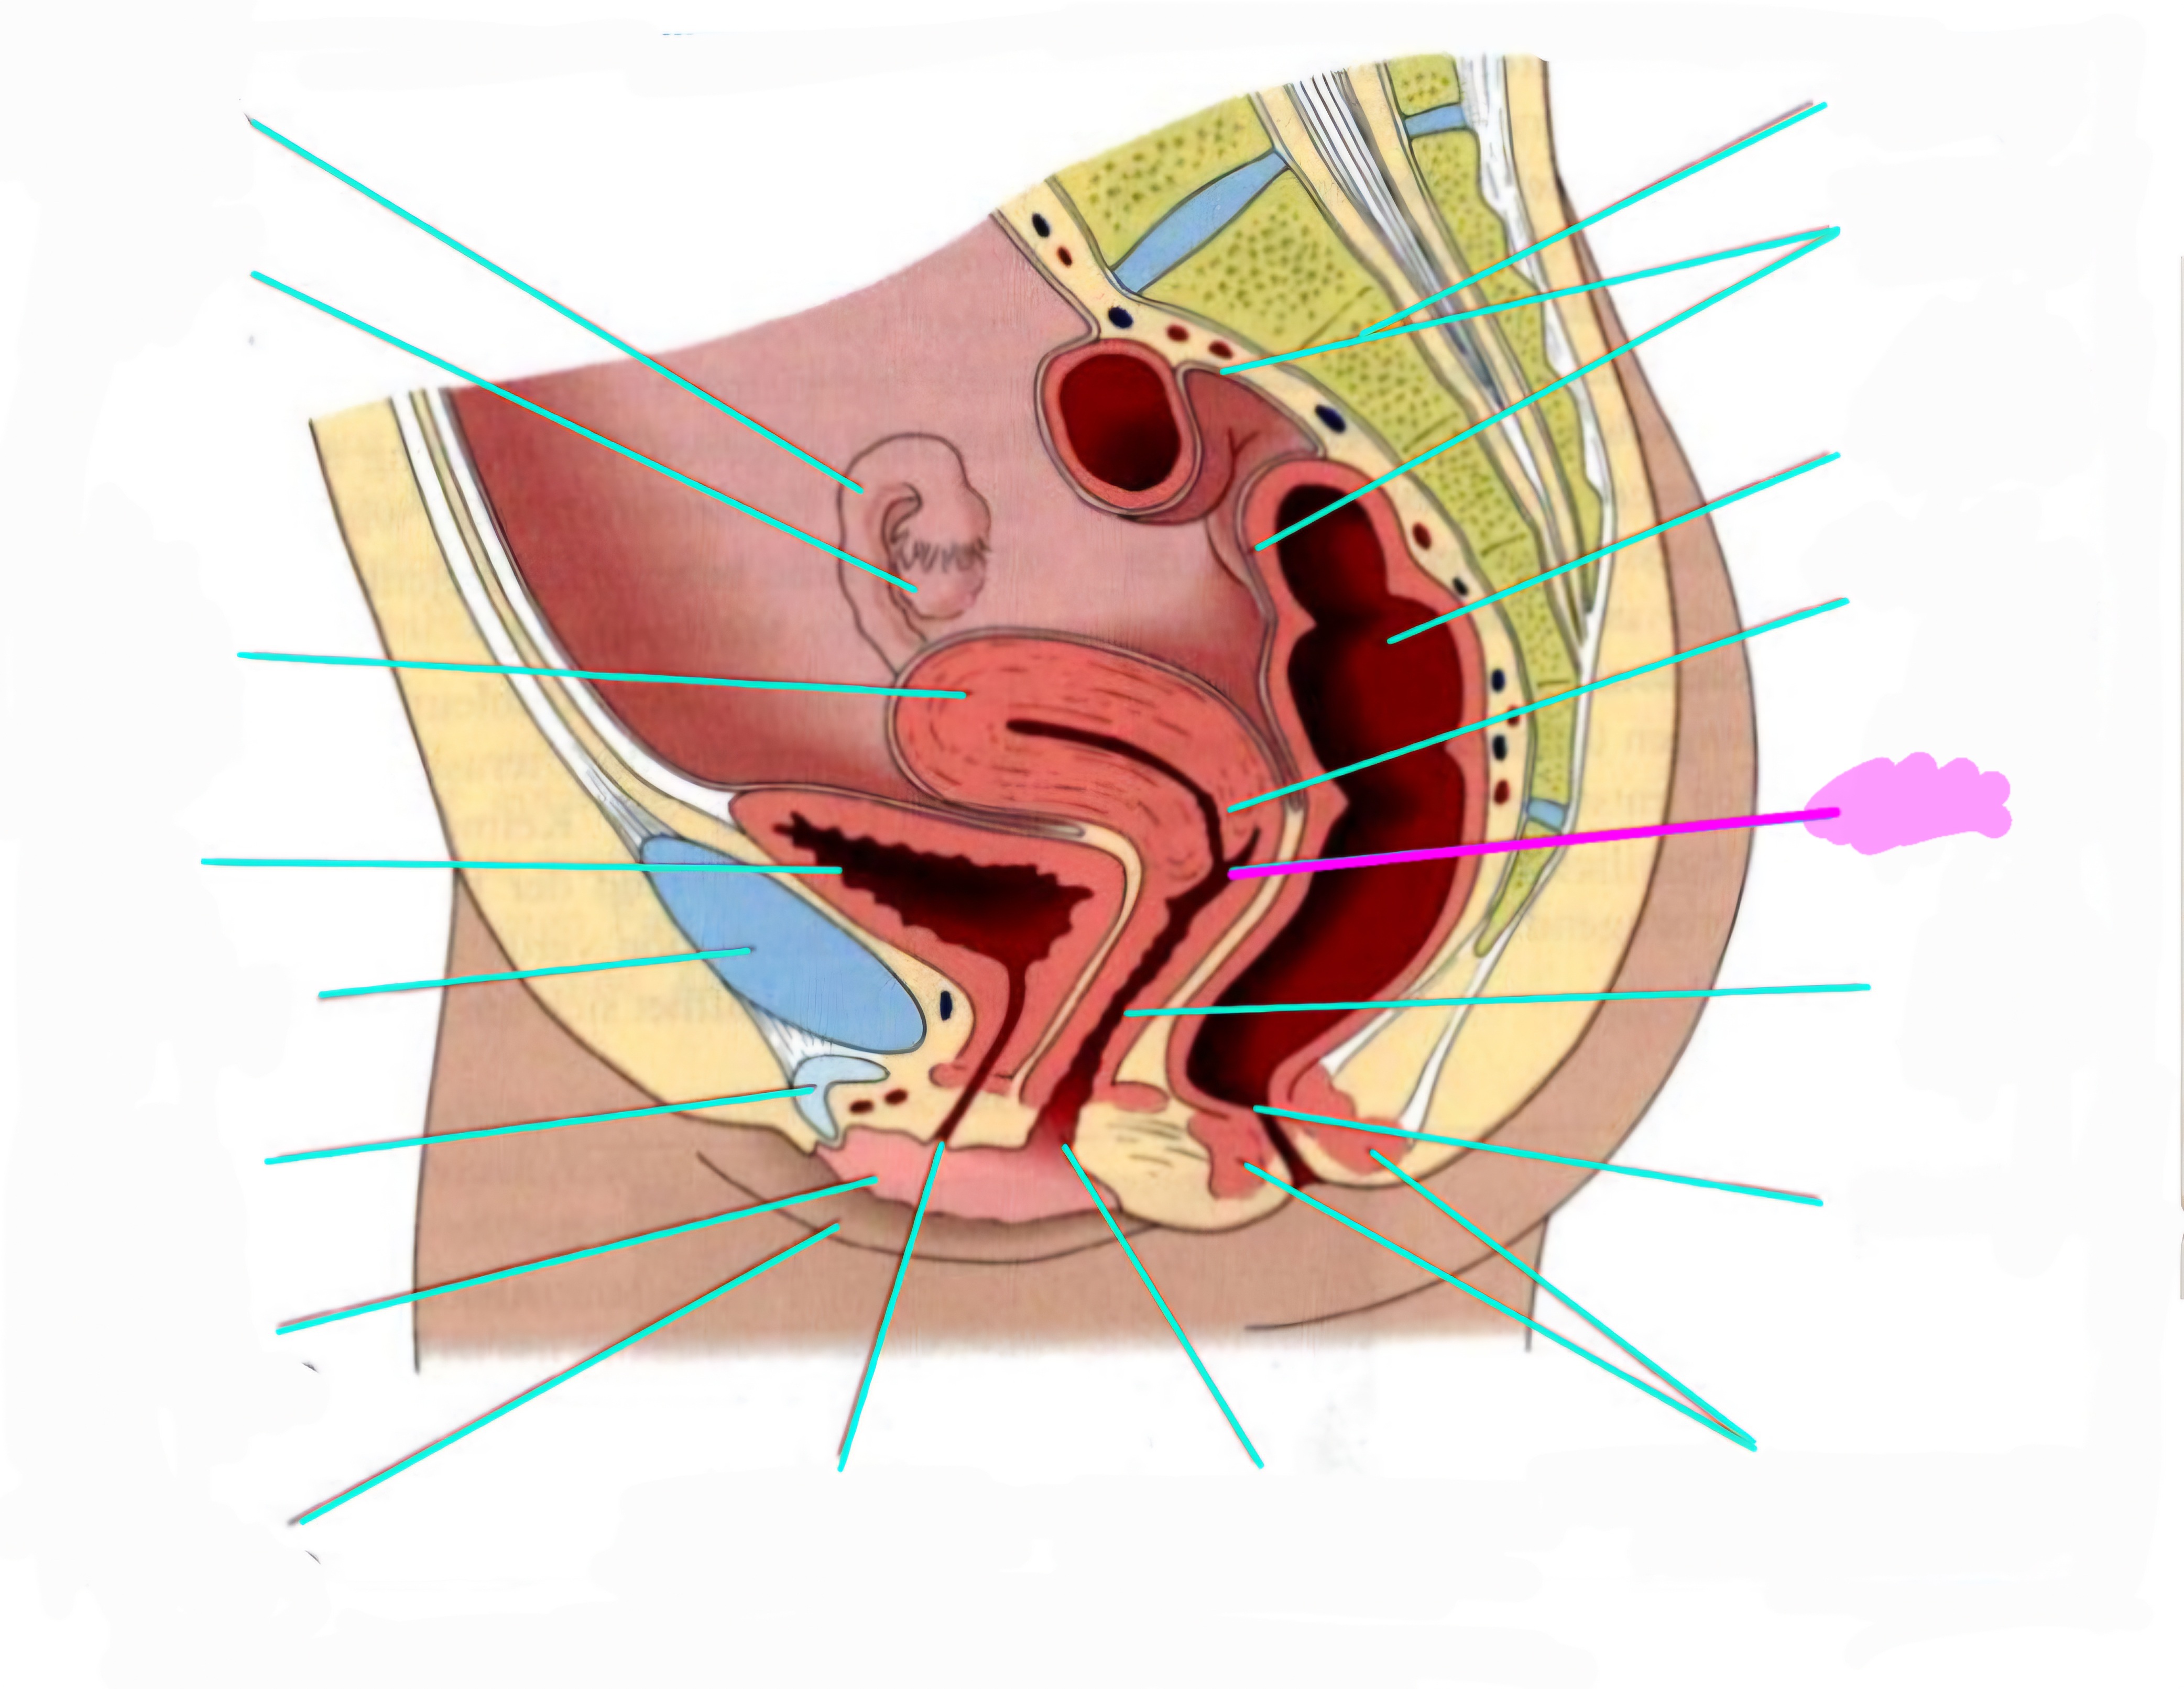

wbl. genital Anatomie

19 Terms

Tubea uterina (Eileiter)

Ovar (Eierstock)

Uterus (Gebärmutter)

Vesica Urinaria (Harnblase)

Symphyse

Klitoris

Labia minor pudendi (kleine schamlippen)

Labia Majoran pudendi (große Schamlippe)

Urethra (Harnröhre)

Introitus vaginae (Scheideneingang)

Sphincter ani externes (äußere Afterschließmuskel)

Anus (After)

Vagina (Scheide)

Portio (äußerer Muttermund)

Rektum (Mastdarm)

Zervix (Gebärmutterhals)

Peritoneum (Bauchfell)

Os sacrum (Kreuzbein)

Uterus: Topographie und Aufbau - wie groß ist er und wo liegt er?

7-8cm lang, Form einer umgedrehten Birne

Lage: im kleinen Becken zwischen Blase und Rektum

Antiversio: nach vorne geneigt, steht im Winkel zur Scheide

Antiflexio: in sich selbst geknickt, nach vorne abgebogen öber die Blase